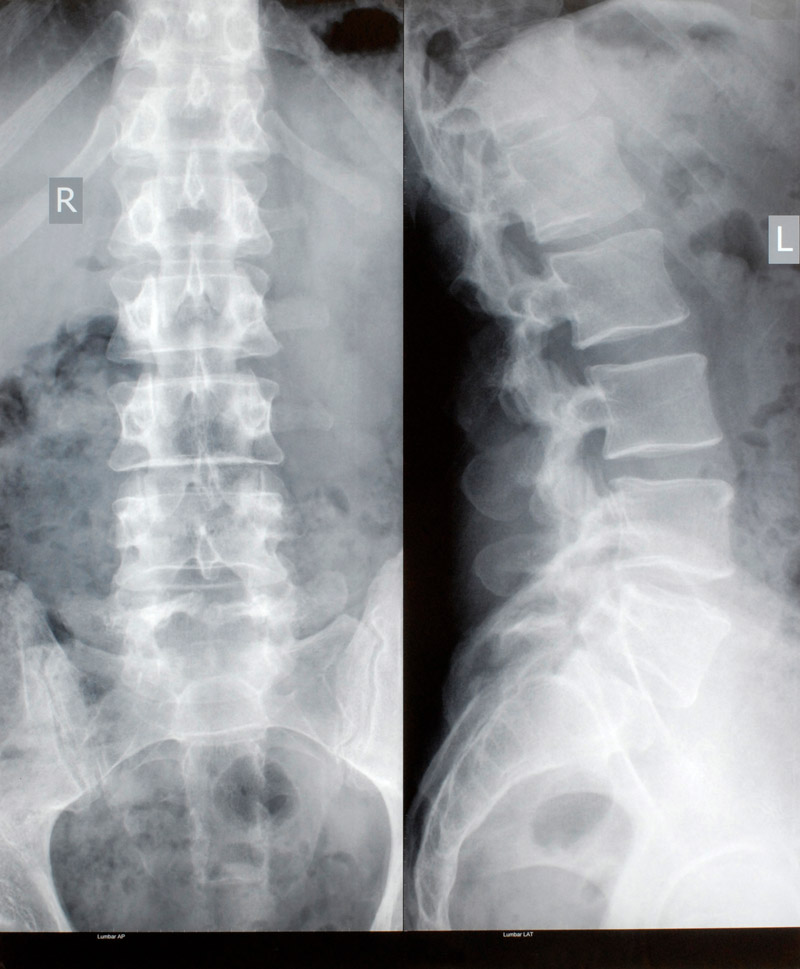

Rückenschmerzen gehören zu den häufigsten Beschwerden überhaupt – sie können durch Verspannungen, Verschleiß oder Bandscheibenprobleme entstehen und die Lebensqualität stark beeinträchtigen. In unserer orthopädischen Praxis sind Sie bei allen Erkrankungen der Wirbelsäule in besten Händen. Unser Ziel ist eine wirksame Schmerzlinderung und die Wiederherstellung Ihrer Beweglichkeit – möglichst ohne Operation. Wir bieten das gesamte Spektrum moderner Diagnostik und Therapie an, von gezielten Injektionen und minimalinvasiven Verfahren unter Monitorkontrolle bis hin zu modernen Operationsmethoden bei Bedarf. Auch spezielle Behandlungen wie Skoliose-Sprechstunde, Stoßwellentherapie oder Verödung von Schmerzfasern kommen zum Einsatz. Vereinbaren Sie jetzt Ihren Termin – für eine starke, schmerzfreie Wirbelsäule.